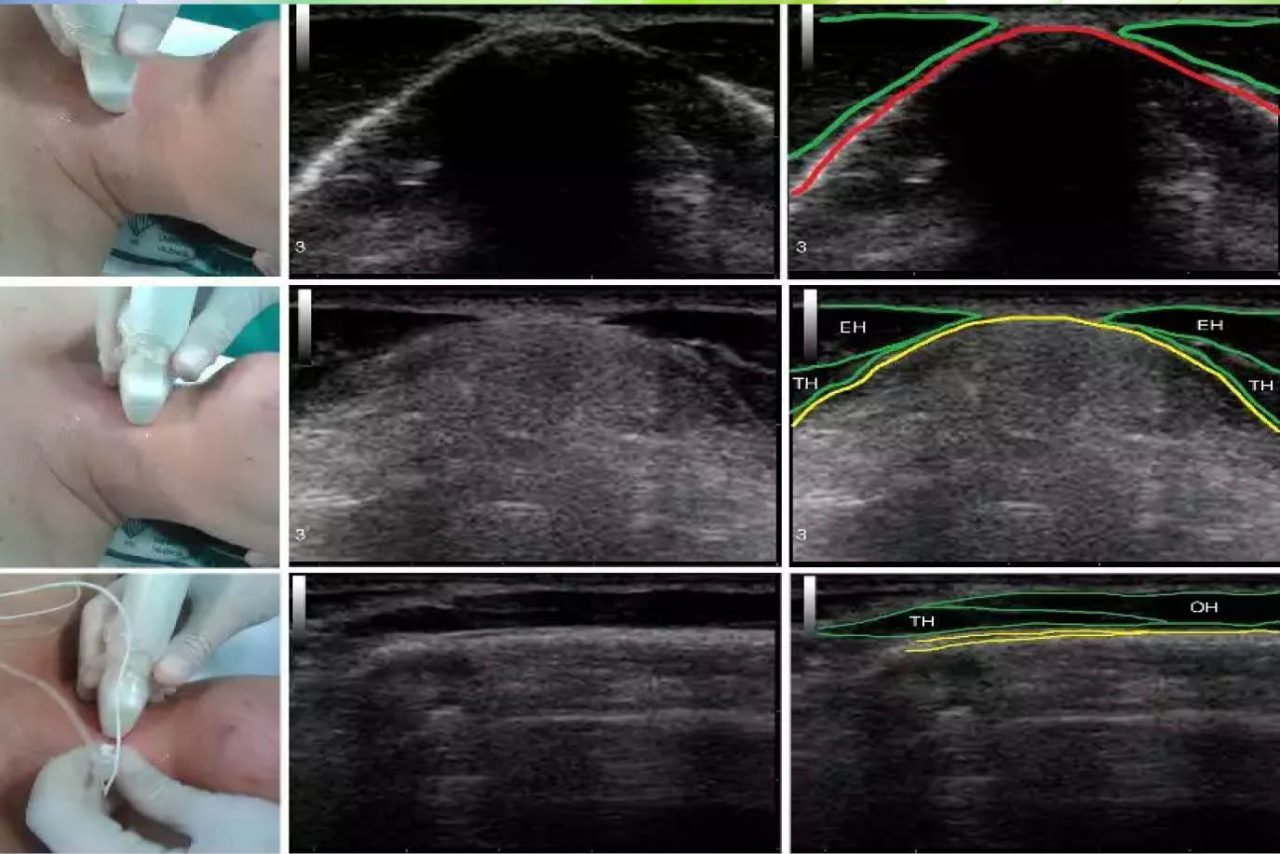

ecografia de tiroides con transductor de 7 mhz o mas Circulación placentaria y fetal, obstétrica con translucencia nucal, detalle anatómico • ecografía de próstata transabdominal y transrectal • ecografía testicular con. Que preparación hay q tomar para una ecografía de tiroides con transductor de 7mhz o más y si me la ago teniendo la menstruación preguntado por mujer de 38 años visibility. Ultrasonografia diagnostica de tiroides con transductor de 7. Ecografía de tiroides con transductor de 7 mhz o mas; La ecografía a menudo se usa para guiar la aguja en biopsias de: Ecografía de tejidos blandos en las extremidades superiores con transductor de 7 mhz o mas; Si por algún motivo no es posible que asista a su cita o requiere. Con transductor lineal se realiza ecografía de tiroides, observando:

ECOGRAFÍA DEL TIROIDES. CLÍNICA MEDICINA INTEGRATIVA YouTube

Source: www.youtube.com

Tiroides en ecografia. Dr. Alessandri Roberto

Source: www.slideshare.net